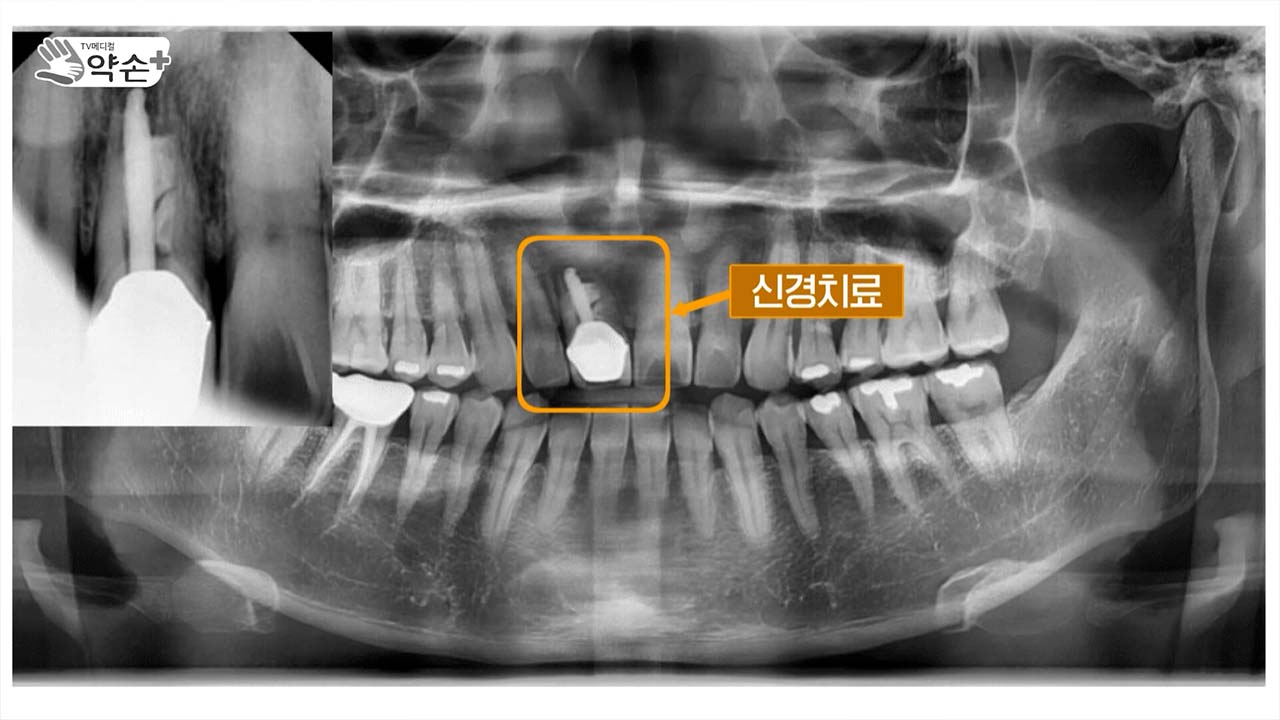

치조골 이식 수술이 필요한 경우에 대해서도 짚어주셨는데, 직접 이 시술을 한 환자분들 사례를 보면 조금 이해가 빠를 것 같습니다.

다음은 40대 초반의 남성인데요. 가운데 치아를 보시면요. 신경치료가 되어 있습니다. 이 부분, 이 치아는 이 환자분이 어렸을 때 외상으로 인해서 이미 한 번 손상이 되었고 이 부분에 염증이 생기고 고름이 난다고 저희 병원에 내원해 주셨습니다. 그래서 검사를 해 봤을 때 이 부분이 많이 흔들리고 더는 이 치아를 유지하기가 힘들어서 발치를 결정하였습니다. 왼쪽 사진이 발치한 직후의 사진인데요. 보시면 치조골이 치아를 발치한 부분 외에도 상당히 소실되어 있습니다. 그리고 오른쪽 사진은 제가 치조골 수술을 하고 임플란트 식립 직전에 잇몸을 열었을 때의 상태입니다. 수평적으로, 수직적으로 치조골이 잘 형성된 사진입니다.